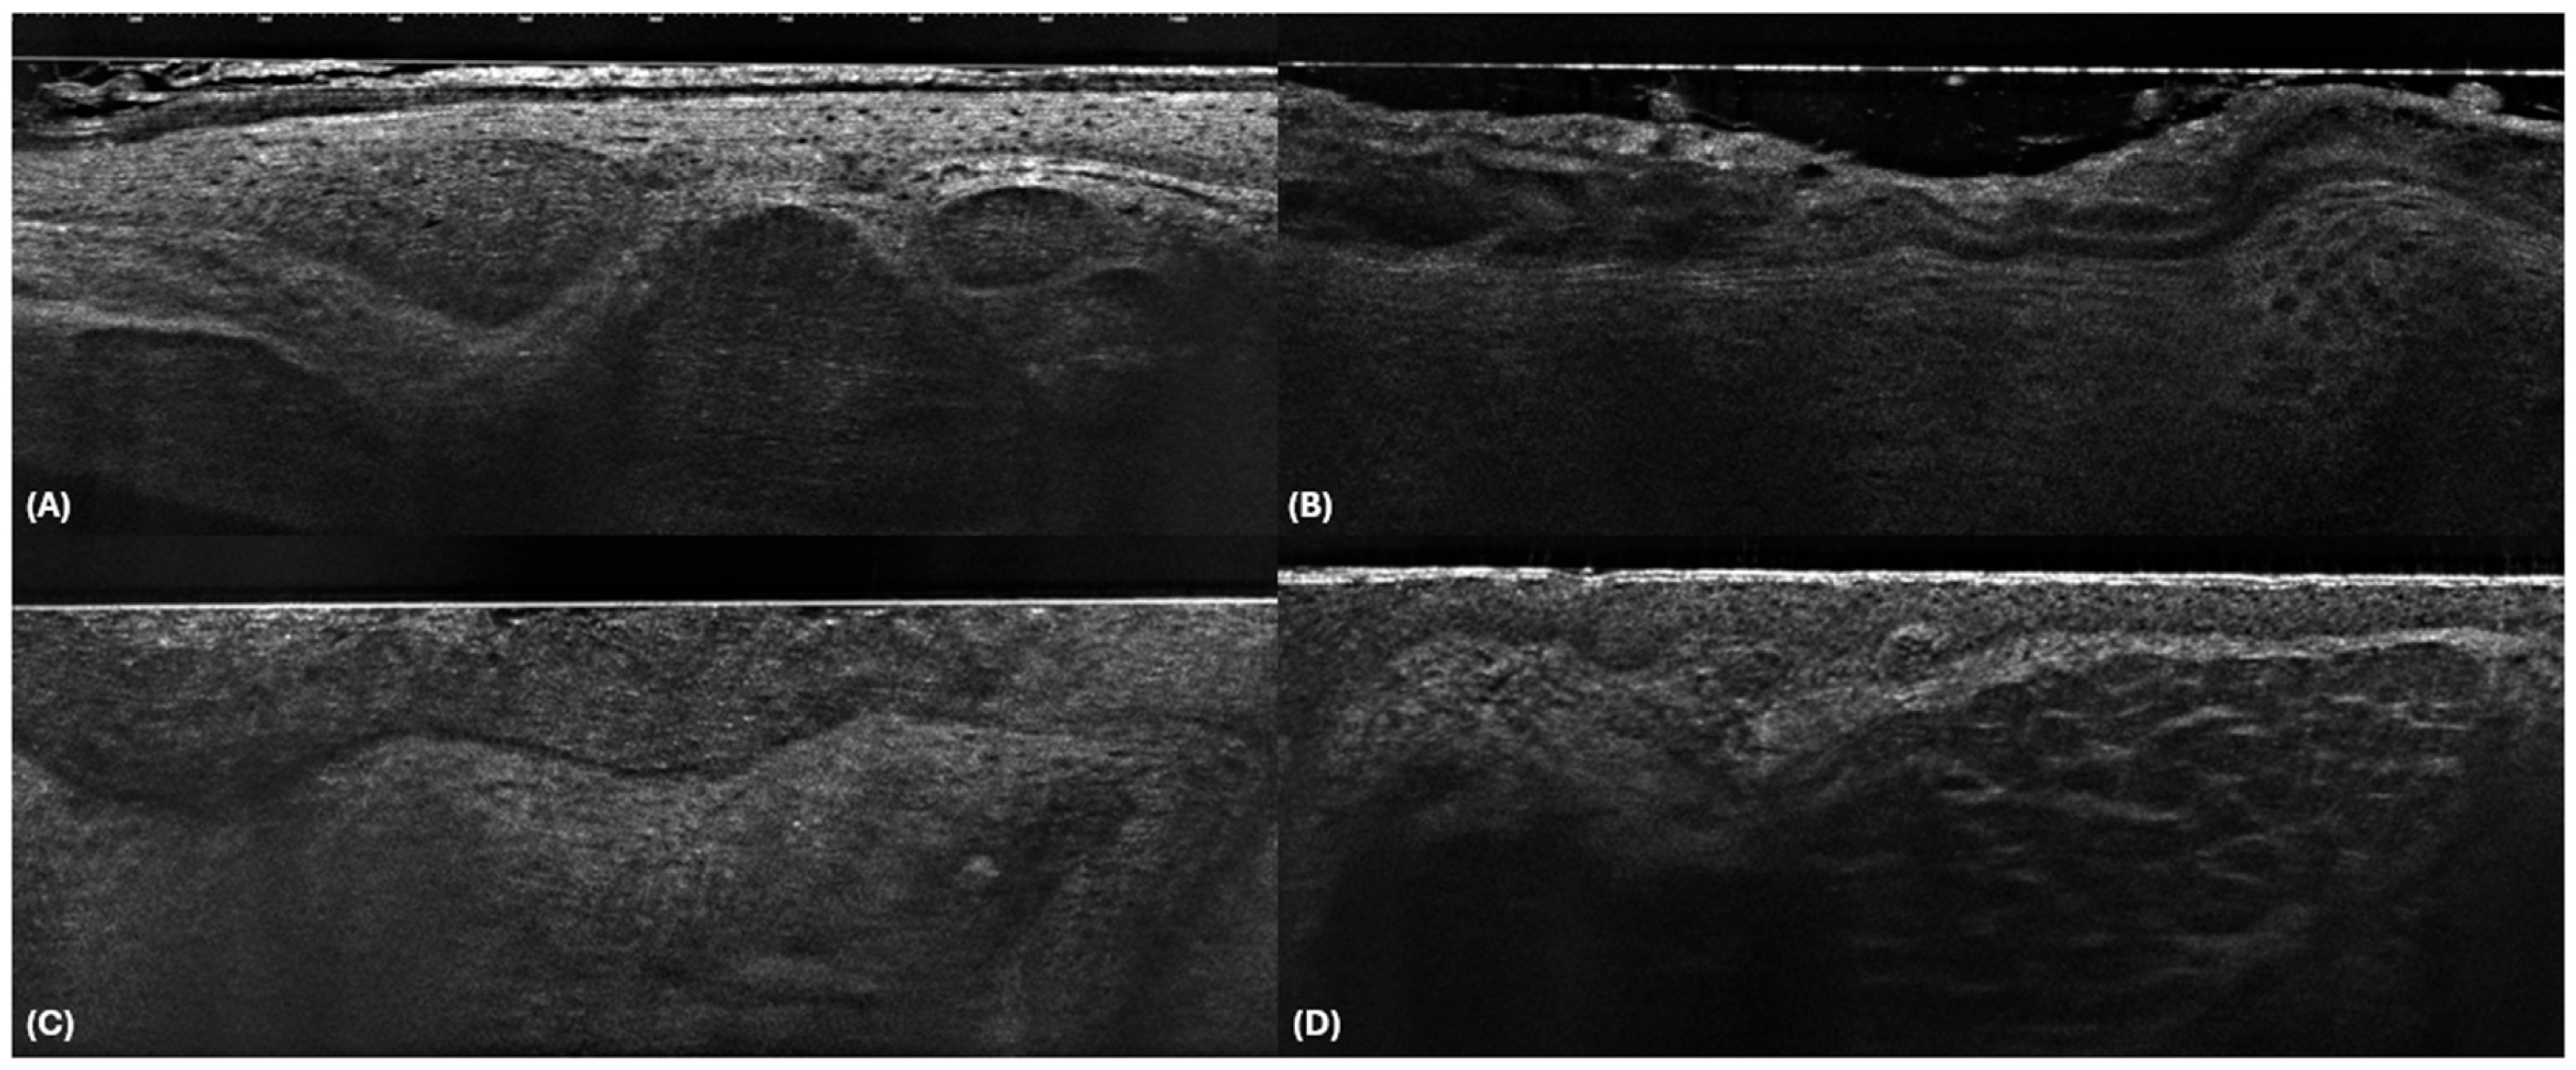

| BCC | Clefting The clefting corresponds to the middle dark rim surrounding the lobule. It probably corresponds to peritumoral mucin deposition. |

| Bright rim The outer rim surrounding the lobule characterised by a brighter colour than the stroma. This appearance is probably due to compression and/or alteration (mass effect) of the collagen fibres of the stroma by the tumour islands. | |

| Millefeuille pattern The cores of BCC lobules correspond to dense cellularity oriented along the same axis, composed of basaloid cells. | |

| BCC subtypes | |

| Superficial |

|

| Nodular |

| Infiltrating |